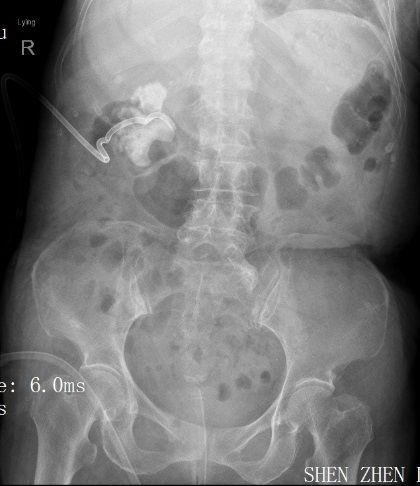

住院后完善检查后发现,患者3年前因右肾结石并积脓感染在外院行右肾穿刺造瘘后1月拔出造瘘管,之后从造瘘管持续流出脓液至今,单单是更换纱布的花费已有2万余元。

因患者存在严重的泌尿系感染,长期感染致使患者出现严重营养不良及毒素缓慢吸收的中毒表现,遂全科讨论后首先尝试行右侧输尿管支架植入术以求内引流控制感染,但效果不佳;果断再次行右侧肾穿刺造瘘引流局部感染物质控制感染!

感染初步得到控制后,

明确患者右侧肾铸形结石

并右侧无功能肾,

黄色肉芽肿性肾盂肾炎( xanthogranulomatous pyelonephritis,XGP) 是一种少见的由细菌感染引起的肾实质及肾周组织慢性非特异性炎性病变,约占所有肾感染的0. 6% ~ 1. 4%,由于发病率不高,缺乏特异的影像学表现,常常被误诊为恶性病变。

当患者出现发热、腰疼、血尿、脓尿、尿路刺激症状以及合并慢性泌尿系梗阻症状时,结合以下声像图改变,包括肾形态饱满、肾盂扩张积水,扩张集合系统内具有低回声,尤其发现病人有泌尿系梗阻原因及肾结石时,可以考虑到XGP 的可能性。CT 和超声造影可能有助于进一步明确疾病的诊断,最终确诊仍需依靠超声引导下穿刺或手术的病理报告。